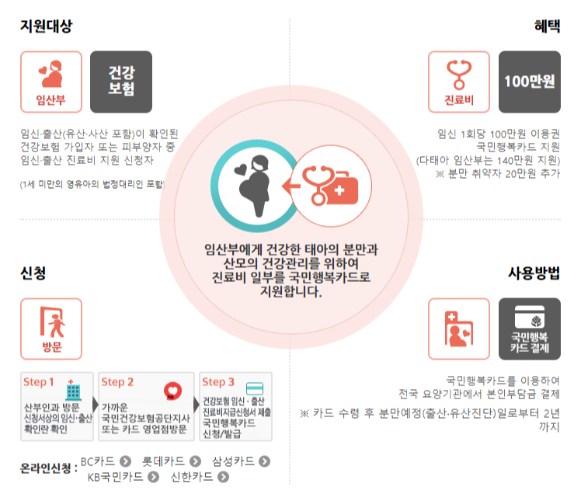

- 국민행복카드 바우처 신청

임신확인서를 발급받았다면,

국민행복카드를 발급해서 임신출산지원금을 신청할 수 있다.

( 단태아 100만원, 다태아140만원 )